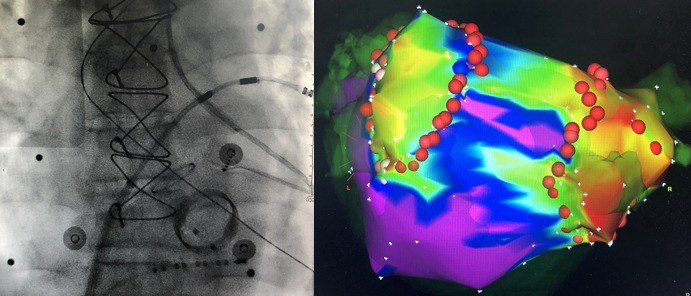

CALA-心律失常激光消融

整合LEONARDO® FPS 激光与LEONARDO® FLOW泵的智能灌注技术,专攻房颤、房扑等复杂心律失常,通过专利CALA光纤实现精准透壁消融。